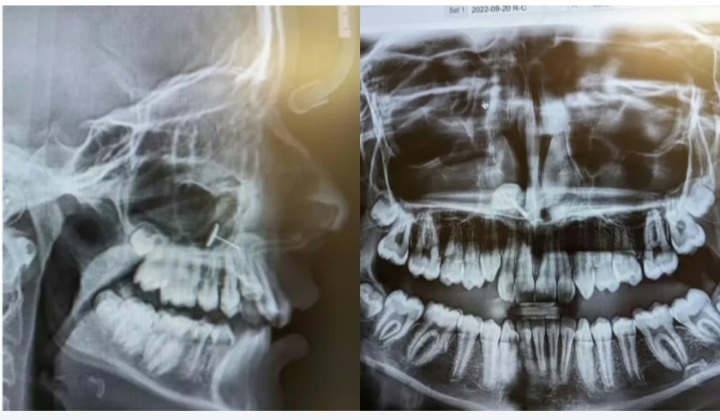

अमेरिका के वॉशिंगटन स्टेट में एक साधारण डेंटल चेकअप एक रहस्यमयी खोज में बदल गया। 13 वर्षीय लड़की को ब्रेसेज लगवाने के लिए उसकी मां ऑर्थोडॉन्टिस्ट के पास लेकर गई थीं। परन्तु एक्स-रे रिपोर्ट में डॉक्टरों को जो दिखा, उसने सभी को चौंका दिया।

ऑर्थोडॉन्टिस्ट द्वारा कराए गए एक्स-रे में बच्ची के साइनस कैविटी में एक धातु का टुकड़ा दिखाई दिया। सामान्यत: साइनस हड्डियों से घिरे हुए वायु-कोष्ठक (air-filled spaces) होते हैं, जिनमें किसी विदेशी वस्तु का पाया जाना बेहद असामान्य है।

ओटोलैरिंजोलॉजिस्ट (ENT विशेषज्ञ) का कहना है कि ऐसे मामलों में तत्काल सीटी-स्कैन और आगे की जांच ज़रूरी होती है। इससे न केवल धातु का आकार और स्थिति स्पष्ट होगी, बल्कि यह भी पता चलेगा कि उसे निकालने के लिए सर्जिकल हस्तक्षेप करना पड़ेगा या नहीं।